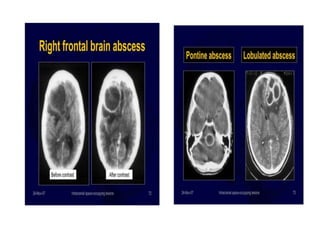

BRAIN ABSCESS

• Mostly single may be multiple

• Majority Supratentorial, 10% infratentorial

DIAGNOSIS

• Method of Choice- CT scan of Brain

– Ring enhancing Lesion